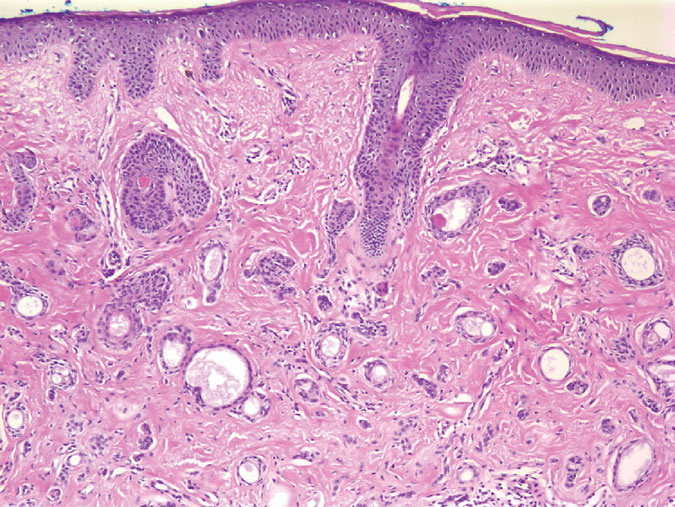

Syringoma = ورم غدي عرقي